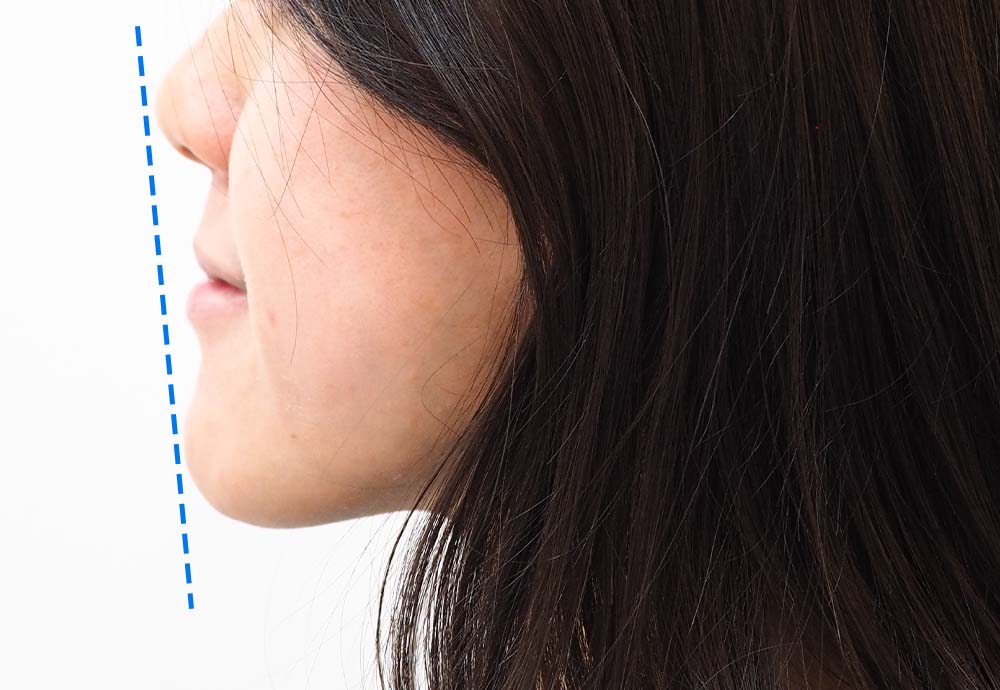

Dental Condition: Protruded side profile

(Facial Profile Analysis)

Unlike metal braces that often rely on extraction to create space, clear aligners allow gentle arch expansion and digitally planned movement (distalization etc) to ensure the least compromise in facial profile.

Perfect if your facial profile makes you unsuitable for extraction.

I didn’t like how my side profile looked after I did my metal braces.

So happy that clear aligners can help me correct that ☺